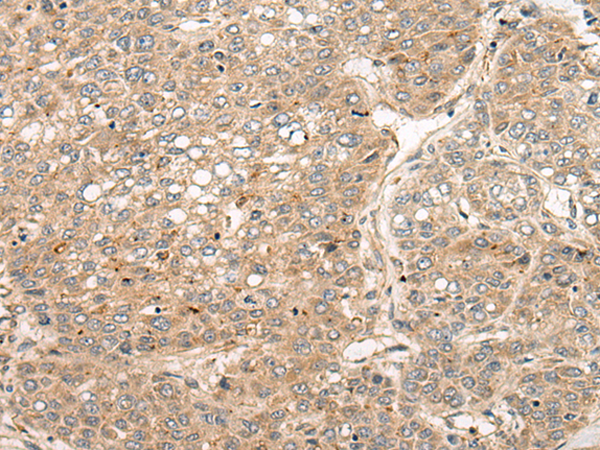

分类: 科研抗体货号: P02443别名: CT3; CT95; CTAG3; bA69L16.7应用: WB,IHC反应种属: Human